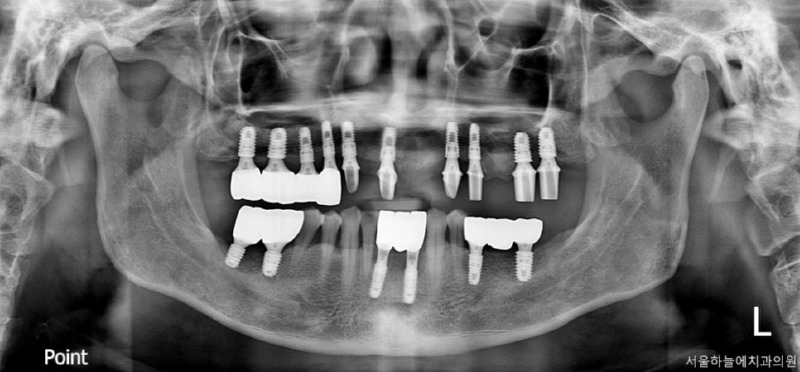

수술 후 4개월

수술 후 6개월 후 보철완료

치료 전 / 치료 후